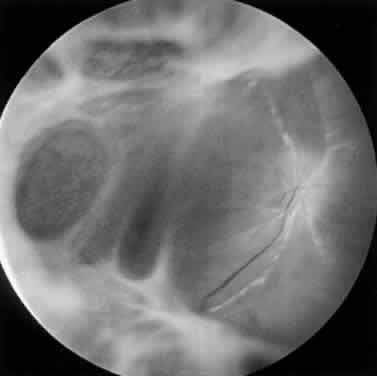

Ultrasonography is invaluable for detecting retinal detachment when the degree of vitritis precludes examination of the posterior segment. In addition, ultrasound may be used to diagnose enlargement of the optic nerve sheath, which occurs with ARN optic neuropathy.28 Color Doppler imaging has identified hemodynamic compromise in the central retinal artery, suggesting that ischemia plays a role in the pathogenesis of ARN.60